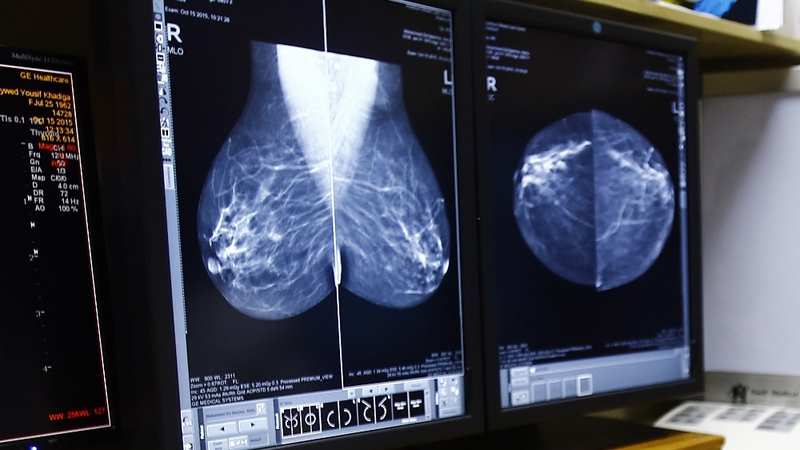

Screening mammography, the most widely used breast cancer screening tool, is an X-ray taken of the breast from multiple views.

An artificial intelligence programme has been developed which can detect breast cancer from mammograms better than experts, a study has found.

A new study has found that an AI system developed by Google Health can identify cancer in breast screening mammograms with fewer false positives, and fewer false negatives than radiologists.